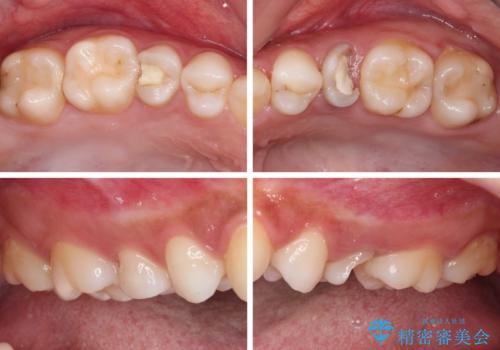

- 根管治療が必要な虫歯を放置した結果、抜歯が必要と診断されたとのことで来院された患者様です。

口腔内の状態やレントゲン写真から判断し、長期的なことを考えると抜歯が無難と思われましたが、それを承知の上で保存するための処置を行うこととしました。

まずは虫歯を除去した上で根管治療を行い、部分矯正により骨内深い位置にまで及んだ健全な部分を引っ張り出すこととしました。